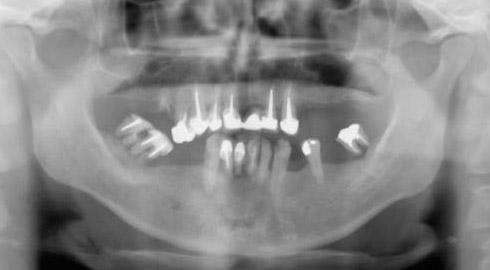

Exemple d’une réhabilitation complète implantaire

Situation clinique terminée